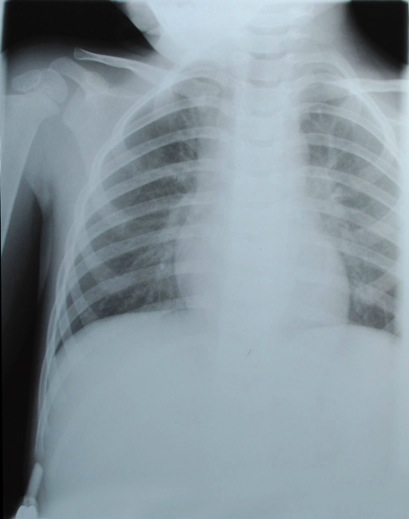

Analyse de radiographies

Radiologie

Analyse différentes radiographies. Essaye de reconnaître:

les différentes parties représentées: os, articulations,...

les malformations, les déplacements, les fractures.

l’âge des sujets: zones de croissances.